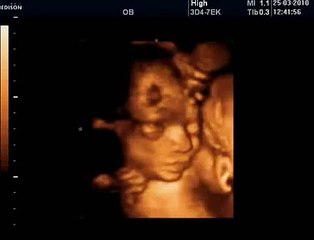

18 Haftalık Gebelik Bebek Ultrason Görüntüsü

Hafta hafta gebelik dönemi 18 haftalık bebek ultrason görüntüsü. Gebelikte 18. hafta daha çok bilgi için sayfamızı ziyaret edebilirsiniz.